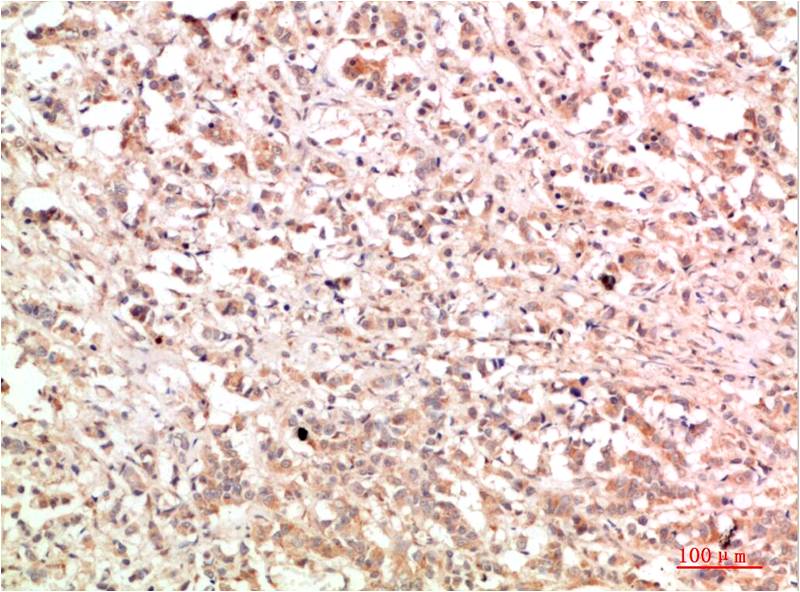

IkB α Rabbit Polyclonal Antibody

Applications :WB, IHC

| Recommended dilutions: | WB 1:500-2,000 IHC 1:50-300 |

| Specificity: | The antibody detects endogenous IkB α protein |